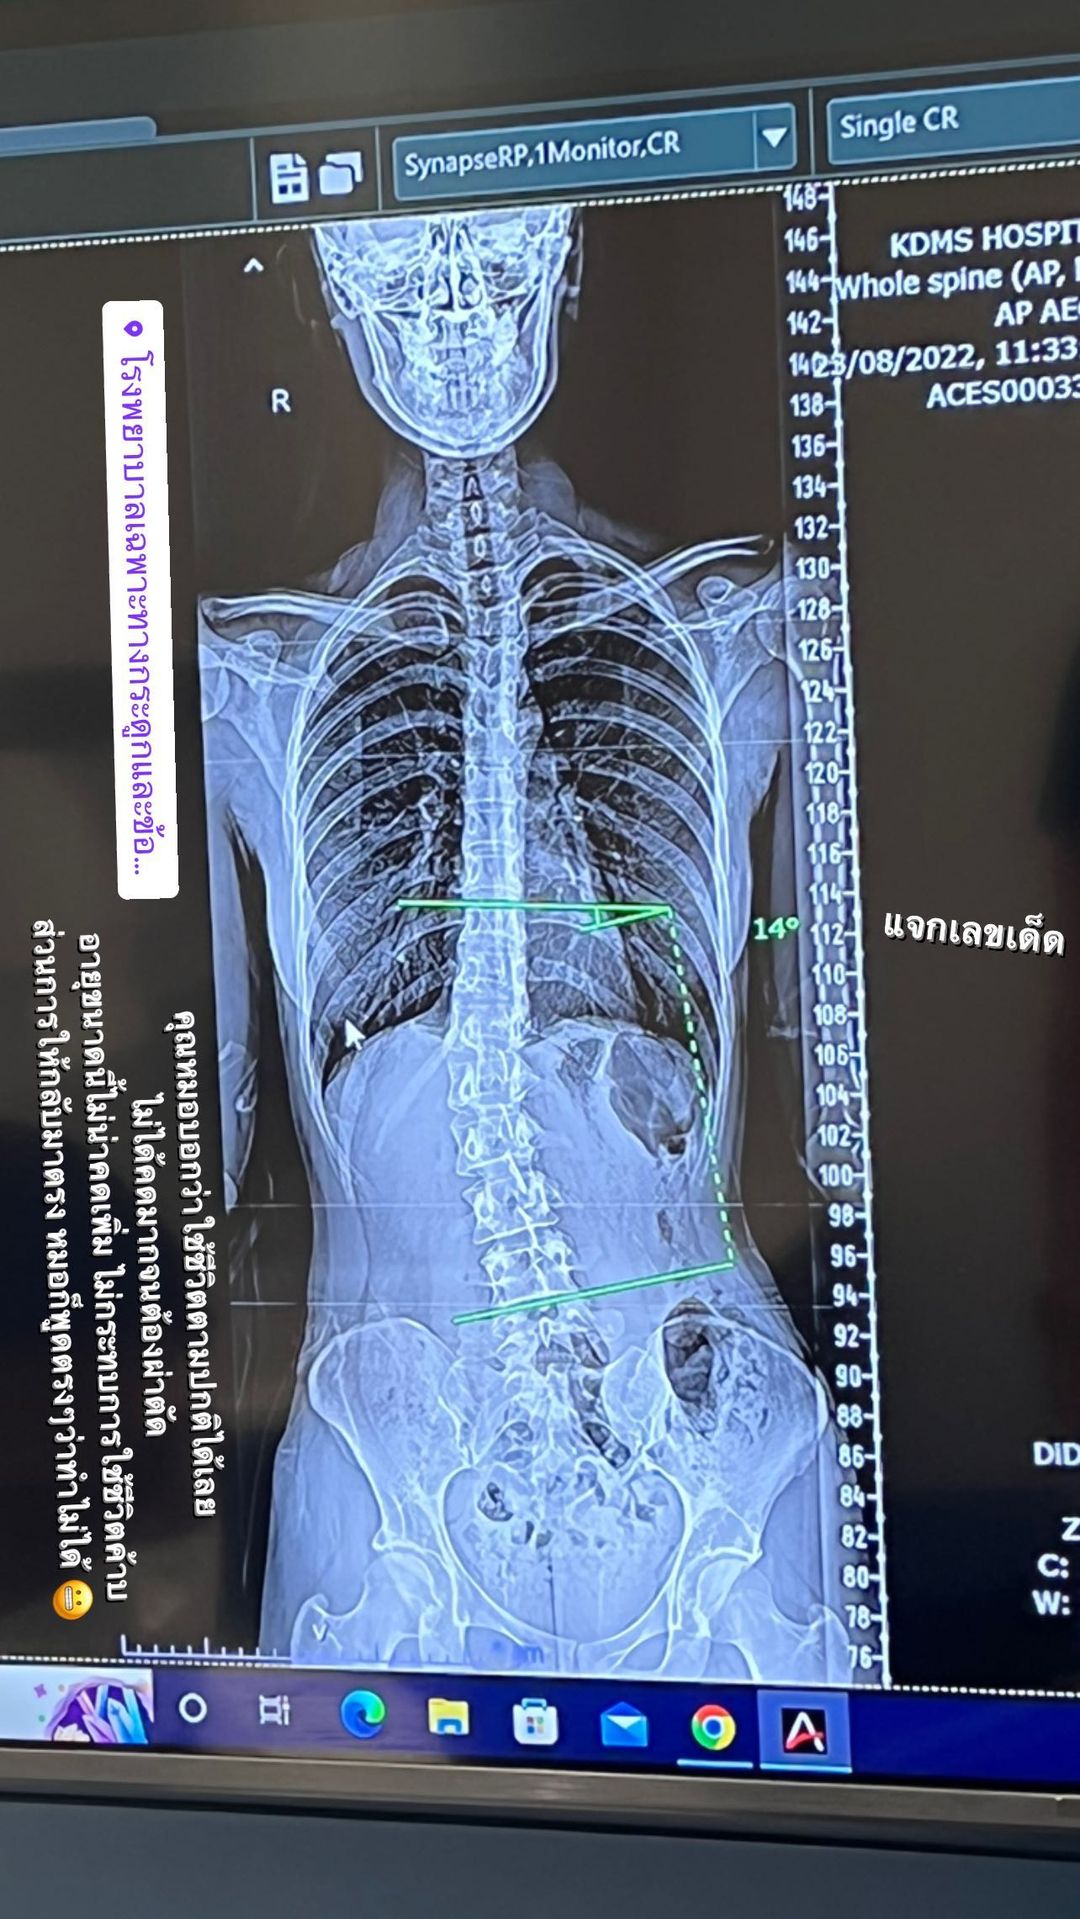

ส้ม มารี โชว์ภาพเอกซเรย์กระดูกให้เห็นชัด ๆ หลังลงรูปโชว์แผ่นหลังแล้วหลายคนตกใจ เผยป่วยกระดูกสันหลังคด ตรวจแล้ว 14 องศา จัดกระดูกไม่ช่วยอะไร

ก่อนที่ล่าสุด (23 สิงหาคม 2565) ส้ม มารี จะออกมาเผยภาพเอกซเรย์กระดูก หลังตัดสินใจไปตรวจกับคุณหมอที่โรงพยาบาลเฉพาะทาง พร้อมเปิดใจเกี่ยวกับอาการกระดูกคดของตัวเอง ดังนี้

"เคล็ดลับเอวเอส.. วัยรุ่นกระดูกคด จริง ๆ รู้ตัวมาหลายปีแล้วว่ากระดูกสันหลังคด เคยตรวจมาก่อน คุณหมอก็บอกว่าไม่ได้ต้องทำอะไร วันนี้ลองมาตรวจอีกสักที สรุปก็คล้ายเดิมฮะ คุณหมอบอกว่า 14 องศาไม่ได้อันตราย และด้วยอายุขนาดนี้ไม่น่าคดเพิ่มแล้ว คุณหมอบอกว่าไม่ต้องทำอะไรค่ะ ใช้ชีวิตไปปกติได้เลย ออกกำลังกายสม่ำเสมอเพื่อให้กล้ามเนื้อแข็งแรง การจะทำให้มันกลับมาตรง คือทำไม่ได้นะคะ เพราะร่างกายเราปรับไปกับโครงสร้างของเราแบบนี้ไปแล้ว และการจัดกระดูกไม่ช่วยอะไรค้าบ"